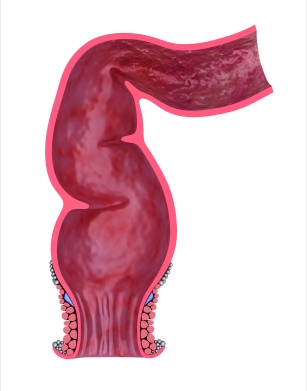

Патология толстого кишечника, связанная с длительным застоем каловых масс в кишечнике в результате постоянных нарушений моторной функции кишки. К запорам приводят пороки развития кишечника, рак толстой кишки, патология нервной системы, особенности питания с резким ограничением растительной пищи.